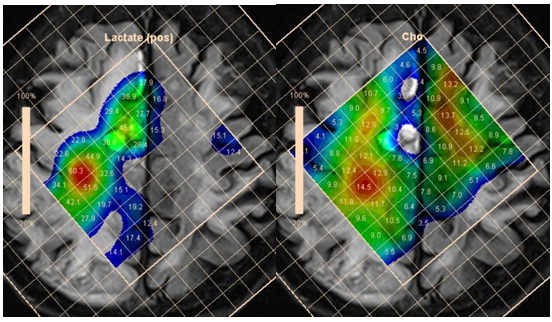

An increase of the myo-inositol level is typical for gliomas. The highest level of myo-inositol shows a relatively benign (grade II) astrocytoma. According to Riyadh et al.,45 the average value of Myo/Cr is 0.49 for benign and 0.33 to 0.15 for anaplastic glioblastoma.45,46 Spectroscopy also provides clinically valuable information for planning stereotactic biopsy (Figure 18), in evaluation of perifocal areas after invasive tumor removal, for radiation therapy planning (Figure 19), and in discrimination between radionecrosis and tumor recurrence (Figure 20). In all these cases, the highest concentration of choline (Cho/NAA and Cho/Cr ratio) is estimated.

Figure 18 Bilateral thalamic astrocytoma. PRESS, TE 30 ms (a) and PRESS, TE 135 ms (b) and map of myo-inositol (c) and choline (d) concentrations, for planning stereotactic biopsy. Histological analysis revealed anaplastic astrocytoma, though high myo-inositol concentration is more typical for grade II gliomas.

Figure 19 Maps of Cho concentrations in patients after removal of anaplastic astrocytoma without evidence of tumor invasion (a), and glioblastoma, with evidence of tumor invasion in the perifocal area (b).